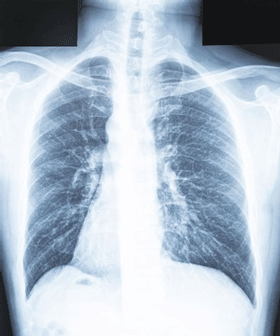

U.S. Tuberculosis Cases Rising Steadily

Tuberculosis cases in the United States have been rising steadily after a rapid decline during the COVID-19 pandemic and are now at a twelve-year high. Healthcare organizations need to evaluate trends in their local area to ensure that employee screening policies are current and effective.

Med Page Today reports that 34 states saw increases in TB cases in 2024. Physicians and healthcare organizations should ensure patients with TB/respiratory symptoms are appropriately screened for risk factors such as exposure and international travel. The increased prevalence of infectious disease may also necessitate a reevaluation of procedures for screening healthcare personnel.